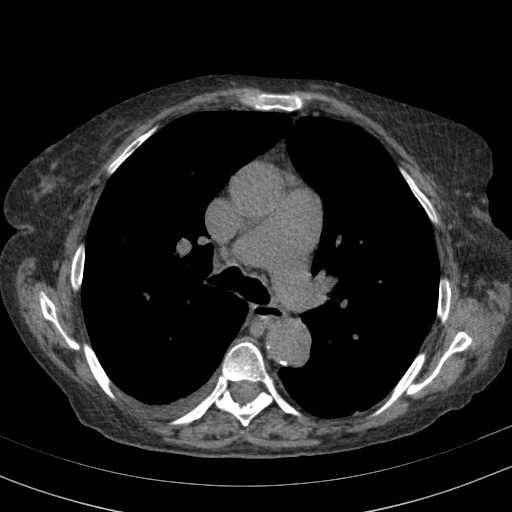

Generated VENOUS CT scan (A→B translation)

Full window (WL 1023.5, WW 4095 β†’ Low βˆ’1024, High +3071)

Lung window (WL -600, WW 1500 β†’ Low βˆ’1350, High +150)